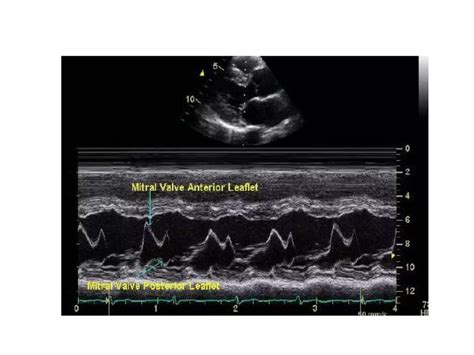

An echocardiogram, or *echo*, is a non-invasive diagnostic test that uses high-frequency sound waves to produce images of the heart. This procedure is invaluable in diagnosing and monitoring mitral stenosis. During a *mitral stenosis echo*, the ultrasound waves bounce off the heart's structures, creating detailed images that can be analyzed by a cardiologist.

Pressure Gradient: The pressure difference between the left atrium and left ventricle is measured. A higher gradient indicates more severe stenosis.

Flow Velocity: The speed of blood flow through the mitral valve is assessed. Higher velocities suggest more severe narrowing.